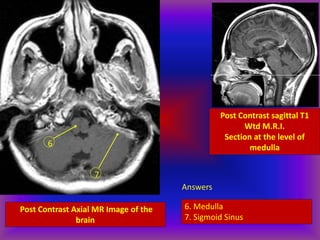

Post Contrast Axial MR Image of the

brain

7

6

Post Contrast sagittal T1

Wtd M.R.I.

Section at the level of

medulla

Answers

6. Medulla

7. Sigmoid Sinus